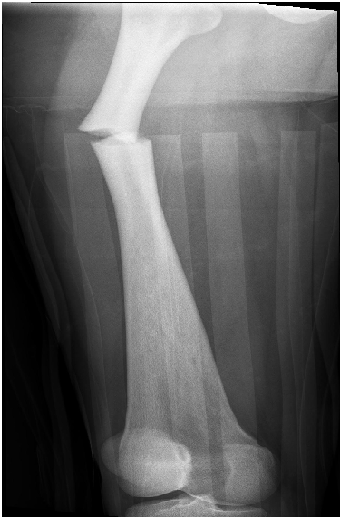

Toulouse-Lautrec Disease: A Case Report of a Femur Shaft Fracture

Etienne Boyer, Gauthier Menu, Thomas Rondot, Fanny Mille, Maxime Ferrier, Antoine Adam, Laurent Obert, Philippe Liverneaux*